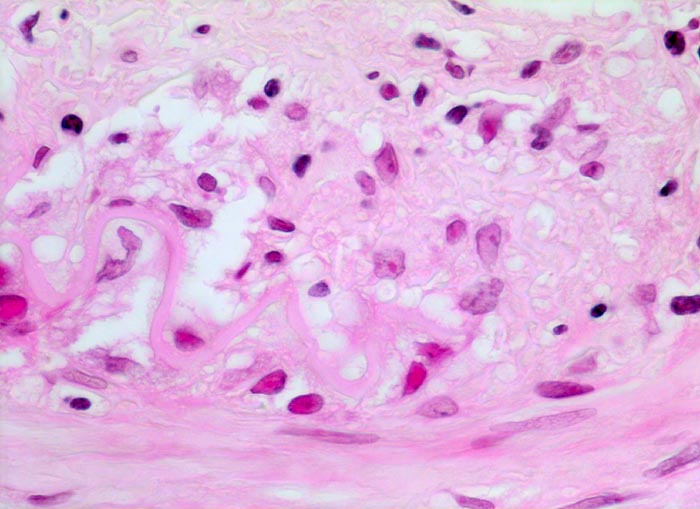

Arteritis temporalis Horton (Riesenzellarteriitis)

Arteria temporalis

An der Grenze zwischen Media und Intima (oben) Reste einer fragmentierten Lamina elastica interna. Lymphozytäres und Histiozytäres Infiltrat im Bereich der Media-Intima Grenze.

Riesenzellen sind nur bei zwei Drittel aller Fälle nachweisbar. Da die Läsionen meist segmental verteilt sind, sollte eine Biopsie idealerweise ein 4-5cm langes Arterienteilstück umfassen. Das Gewebe wird vollständig eingebettet und mit Stufenschnitten untersucht.

630